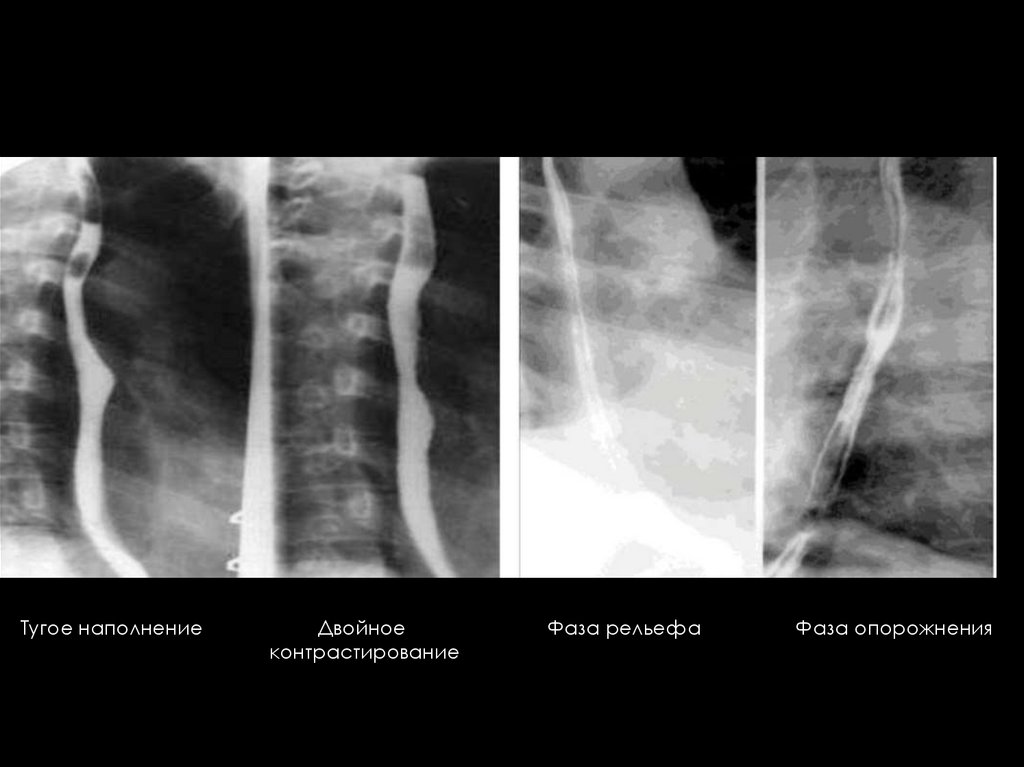

12. МЕТОДИКА РЕНТГЕНОЛОГИЧЕСКОГО ИССЛЕДОВАНИЯ ОРГАНОВ ЖКТ И ФАЗЫ КОНТРАСТИРОВАНИЯ

Фазы контрастирования:

-Тугое заполнение - изучается форма, положение,

контуры, двигательная активность органа);

-Фаза рельефа слизистой оболочки;

-Фаза двойного контрастирования (воздух и малое

количество бариевой взвеси) – изучается толщина

стенки и рельеф слизистой органа.

Одномоенмнтное двойное контрастирование

Тугое наполнение

Двойное

контрастирование

Фаза рельефа

Фаза опорожнения